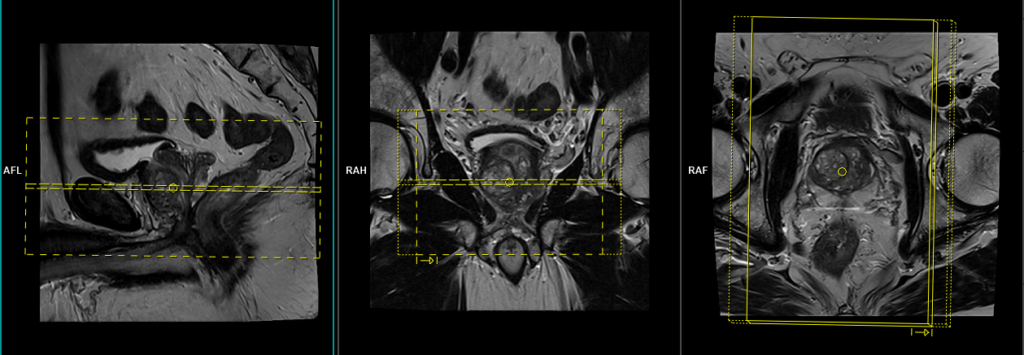

T2 tse coronal 3mm SFOV

Plan the coronal slices on the sagittal plane and angle the positioning block vertically across the prostate, as shown in the picture. Check the positioning block in the other two planes, ensuring an appropriate angle is given in the axial plane (parallel to the right and left hip joints or ischial tuberosity). The slices must be sufficient to cover the entire prostate and seminal vesicles. Additionally, to minimize artifacts stemming from arterial pulsation and breathing, consider incorporating saturation bands on the top and front of the coronal block.

Parameters

TR 3000-4000 | TE 100-120 | SLICE 3 MM | FLIP 130-150 | PHASE R>L | MATRIX 320X256 | FOV 180-230 | GAP 10% | NEX(AVRAGE) 5 |

T2 tse axial 3mm SFOV prostate (straight axial)

Plan the axial slices on the sagittal plane; angle the positioning block horizontally across the prostate (i.e., parallel to the base of the penis). Check the positioning block in the other two planes. An appropriate angle must be given in the coronal plane (parallel to the right and left femoral heads). Slices must be sufficient to cover the whole prostate and seminal vesicles. Additionally, to minimize artifacts arising from arterial pulsation, peristalsis, and breathing, consider incorporating saturation bands on top and in front of the axial block.

TR 4000-5000 | TE 100-120 | SLICE 3 MM | FLIP 130-160 | PHASE R>L | MATRIX 320X288 | FOV 180-200 | GAP 10% | NEX(AVRAGE) 4 |

T2 tse sagittal 3mm SFOV prostate

Plan the sagittal slices on the axial plane, angling the positioning block parallel to the interpubic fibrocartilage and the anal canal. Check the positioning block in the other two planes, ensuring an appropriate angle is given in the coronal plane (parallel to the interpubic fibrocartilage). The slices must be sufficient to cover the entire pelvis from the right acetabulum to the left acetabulum. The field of view (FOV) must be large enough to encompass the prostate and seminal vesicles (typically 180mm-200mm). Additionally, to minimize artifacts arising from arterial pulsation, peristalsis, and breathing, consider incorporating saturation bands on the top and front of the sagittal block.

TR 4000-5000 | TE 100-120 | SLICE 3 MM | FLIP 130-160 | PHASE A>P | MATRIX 320X320 | FOV 180-200 | GAP 10% | NEX(AVRAGE) 4 |